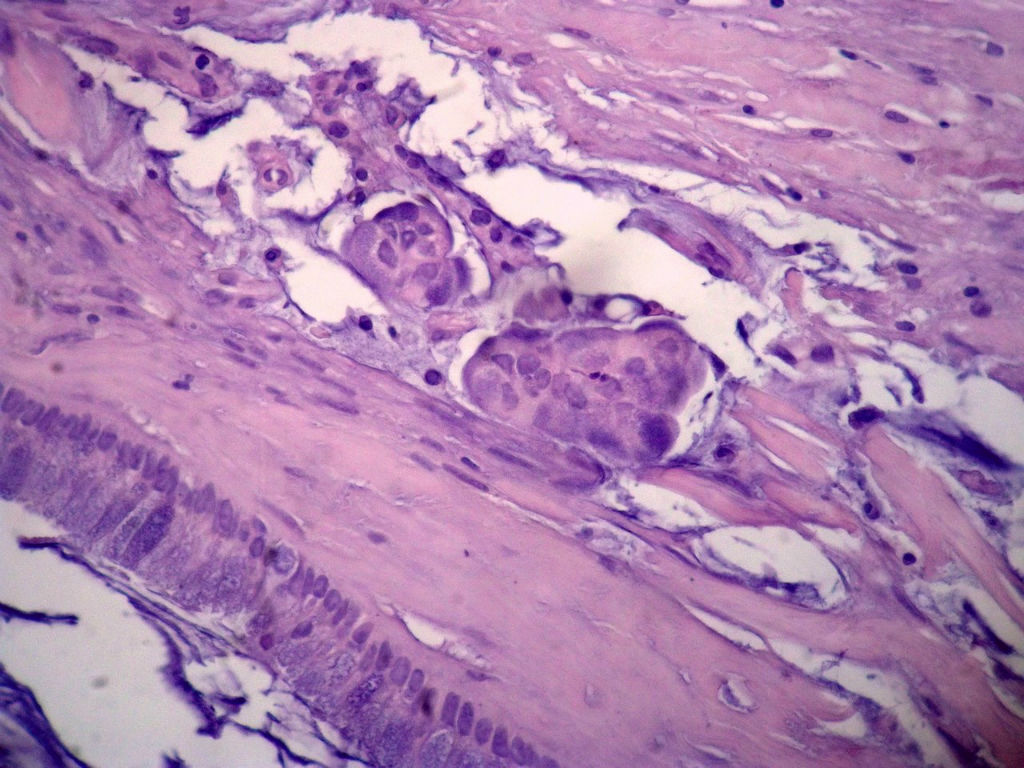

女,80岁,阑尾区肿块。

送检为不规则组织多块,粘滑,解剖结构辨认不清。术中探查双侧卵巢无异常。

• 女,80岁,阑尾区肿块。图2

图2

阑尾粘液性肿瘤,癌的可能性大

粘液长在肌层,而且漂浮着可疑上皮细胞,最大可能粘液腺癌。